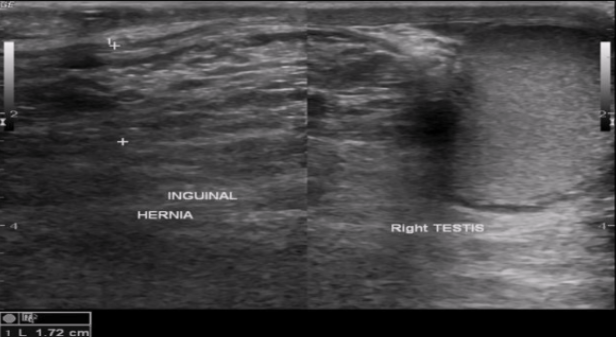

Inguinal hernias

Most common location for a hernia (~75% of all hernias)

Location: near internal inguinal ring, surrounding inferior epigastric vessels (IEV)

Medial to IEV: direct inguinal hernia

Lateral to IEV: indirect inguinal hernia

Indirect inguinal hernia

Most common form of hernia

Occurs lateral to IEV

Congenital hernia

20x more common in men than women

Can extend into the scrotum in men and labia majora in women

More likely to become strangled than direct inguinal

⅓ are bilateral, but are more common on the right side if unilateral

Scrotal hernia

Indirect inguinal hernia → can extend down to the scrotum